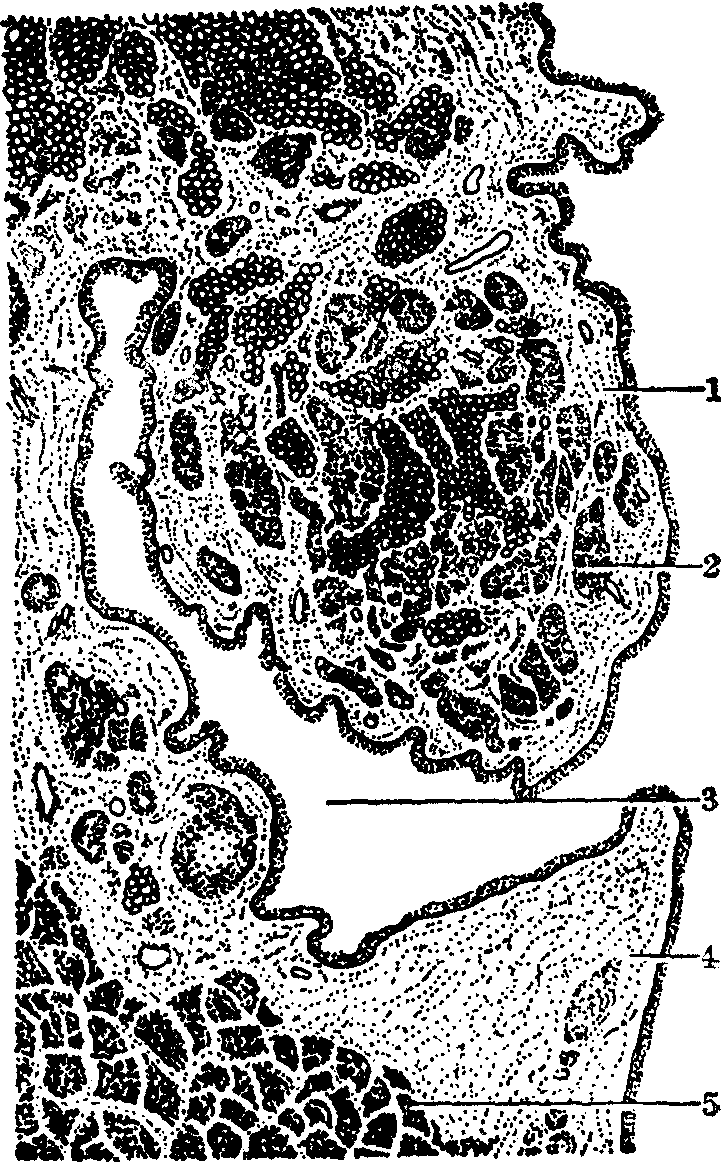

喉腔 大部分被覆假复层纤毛柱状上皮,纤毛向口腔方向摆动,有杯状细胞。固有层为疏松结缔组织,内有大量弹性纤维,并有淋巴组织、浆细胞、肥大细胞等。粘膜下层为疏松结缔组织,与软骨膜相连,其中有小型混合腺(见图)。

喉的结构(额状切面)

1.前庭襞 2.腺 3.喉室 4.声襞 5.声带肌

前庭襞 又称假声带。粘膜上皮为假复层纤毛柱状上皮,有形状细胞。固有层及粘膜下层为疏松结缔组织,内有丰富的混合腺和淋巴组织。

声襞 又称真声带,是一对有弹性的粘膜皱襞。粘膜上皮为不角化的复层鳞状上皮,固有层结缔组织致密,内含大量由前后走向的弹性纤维构成的声韧带,无腺。深部有声带肌,为骨胳肌。声襞受出入空气作用,发生振动而发声。喉肌的收缩可引起喉软骨的运动,从而使声皱襞的紧张度发生改变。声襞的紧张度及呼出气流的变化均可影响音调的变化。咽、鼻腔和口腔都具有共鸣作用,可加强喉所发出声音。声襞下的喉下腔粘膜下层为疏松结缔组织,炎症时,尤其是儿童,最易发生水肿。

喉室 喉室粘膜衬有假复层纤毛柱状上皮,固有层内可见淋巴组织和混合腺,其分泌物有滑润声带的作用。